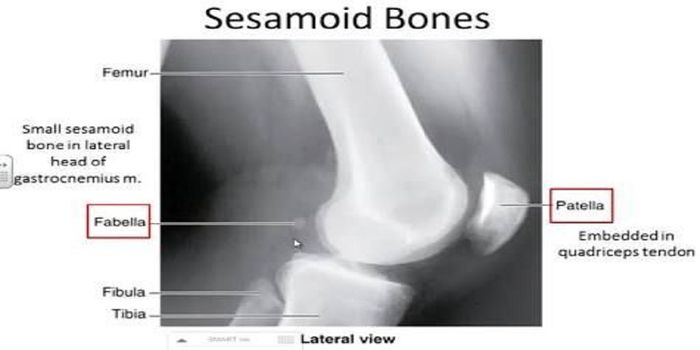

APR 21, 2019Health & MedicineSesamoid bones are embedded in a tendon or muscle, and they are located in areas that have "high mechanic ...